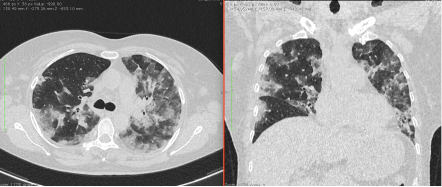

- Изменения в легких при КТ (рентгенографии), типичные для вирусного поражения (объем поражения значительный или субтотальный; КТ 3 - 4)

- Изменения в легких при КТ (рентгенографии), типичные для вирусного поражения критической степени (объем поражения значительный или субтотальный; КТ 4) или картина ОРДС.

КТ имеет высокую чувствительность в выявлении изменений в легких, характерных для COVID-19. Применение КТ целесообразно для первичной оценки состояния ОГК у пациентов с тяжелыми прогрессирующими формами заболевания, а также для дифференциальной диагностики выявленных изменений и оценки динамики процесса. КТ позволяет выявить характерные изменения в легких у пациентов с COVID-19 еще до появления положительных лабораторных тестов на инфекцию с помощью МАНК. В то же время, КТ выявляет изменения легких у значительного числа пациентов с бессимптомной и легкой формами заболевания, которым не требуется госпитализация. Результаты КТ в этих случаях не влияют на тактику лечения и прогноз заболевания при наличии лабораторного подтверждения COVID-19. Поэтому массовое применение КТ для скрининга асимптомных и легких форм болезни не рекомендуется.

4. Все выявляемые при лучевых исследованиях признаки, включая КТ-симптомы, не являются специфичными для какого-либо вида инфекции и не позволяют установить этиологический диагноз. Вне клинической (эпидемической) ситуации они не позволяют отнести выявленные изменения к пневмонии COVID-19 и дифференцировать их с другими пневмониями и невоспалительными заболеваниями. Данные лучевого исследования не заменяют результаты обследования на РНК SARS-CoV-2. Отсутствие изменений при КТ не исключают наличие COVID-19 и возможность развития пневмонии после проведения исследования.